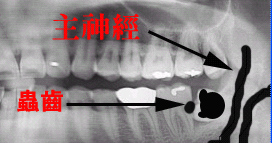

썩은 사랑니 때문에 어금니에 충치가 있다.

사랑니는 뽑았지만 어금니가 문제다.

양치질로 치료가 될까요?